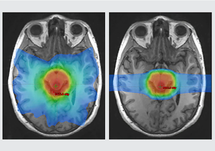

With proton treatment, we’re using a whole different energy particle. Proton is the center of a nucleus and it’s positively charged; we use actually a hydrogen atom that we accelerate to be able to go to the depth that we need it to go to treat these tumors. But because it’s positively charged in comparison to X-rays, which have no charge, because it’s positively charged, we can actually use magnets that are negative and positively charged to pull the proton around, putting a negative magnet in front of a positive proton pulls it forward. So we can time and tune magnets to accelerate these protons so, within two seconds, they’re two-thirds the speed of light and have gone around the earth approximately ten times and then are ready to be angled and pointed at the tumors that we need them to go to. And based on how fast we accelerate those protons, that determines how deep they will go. And so instead of going through you, they will go an inch or a centimeter or two inches or eight inches, depending on how fast we accelerate the proton and then it stops, and you don’t have that exit dose. So if you put film on the backside of the someone and you’re shooting from the front, the film would not be exposed. You could stand behind somebody and not get radiated with the proton treatments. So because of that, we’re able to reduce the unnecessary radiation exposure that people receive when they’re getting radiation treatments.

We talked about how precise proton treatment can be, but because we can direct it, we can make it stop exactly where we want to and that reduces the radiation exposure to normal areas of the brain. But if we can’t find or localize the treatments, then it’s like we don’t have a sight on our sniper rifle. We have this super precise machinery, but without the best imaging, we may not be able to take full advantage of the capabilities of this highly accurate machine. So we’ve also been studying different ways that we can find tumors that are hiding in our traditional imaging, most tumors are found with CT’s or MRIs, but in radiation oncology, we’ve learned over many years of studying tumors and how they regrow or recur that there are often fingers or tentacles of the tumor that we can’t see that are, kind of, the root system of the tumor that we can’t see mixed in with normal brain or normal muscle or normal bone, depending on where the tumor is.

There are advanced treatments, specialized PET scans, for example. We use amino acid PET scan called F-DOPA that we have been able to use to see brain tumors, for example, that are hidden in normal brain that are not visible on MRI. There are other advanced types of MRIs where things are done to find areas of high blood flow or changes in basically the pressure or elasticity that would suggest there’s other things beside normal muscle mixed in with the muscle that you’re seeing on an MRI elastography, so there are newer imaging techniques that help us take full advantage of the highly accurate and precise radiation that we’re able to do now.